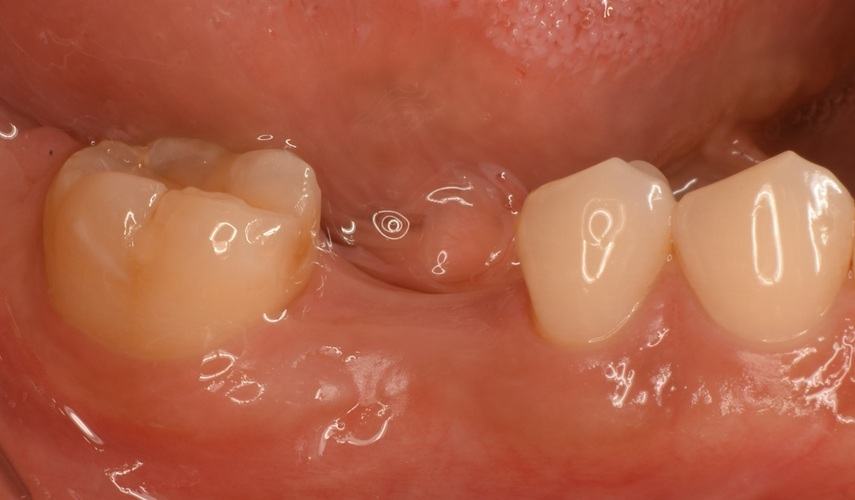

Case4

術前

術中

術後

| 治療名 | GBRとインプラントを行った症例 |

|---|---|

| 治療説明 | インプラントを埋入予定の部位において、骨の吸収が見られたため、インプラント埋入と同時に小規模な骨造成(GBR)を行いました。治癒期間を経て、最終的にセラミックの上部構造を装着し、自然な見た目としっかりとした噛み合わせを回復しました。 |

| 治療回数・期間 | 6ヶ月 |

| 副作用とリスク | インプラント治療は、入れ歯やブリッジに比べて治療期間が長くなる傾向があります。骨造成が必要な場合は、さらに治療期間が延びることがあります。 また、手術後には一時的な違和感や痛み、腫れ、出血などが生じる場合がありますが、通常は2日〜1週間ほどで落ち着きます。 |

| 料金(税込) | GBR〈小規模骨造成〉:110,000円 インプラント一次手術:220,000円 二次手術:55,000円 上部構造〈セラミック〉:165,000円 合計:550,000円 |